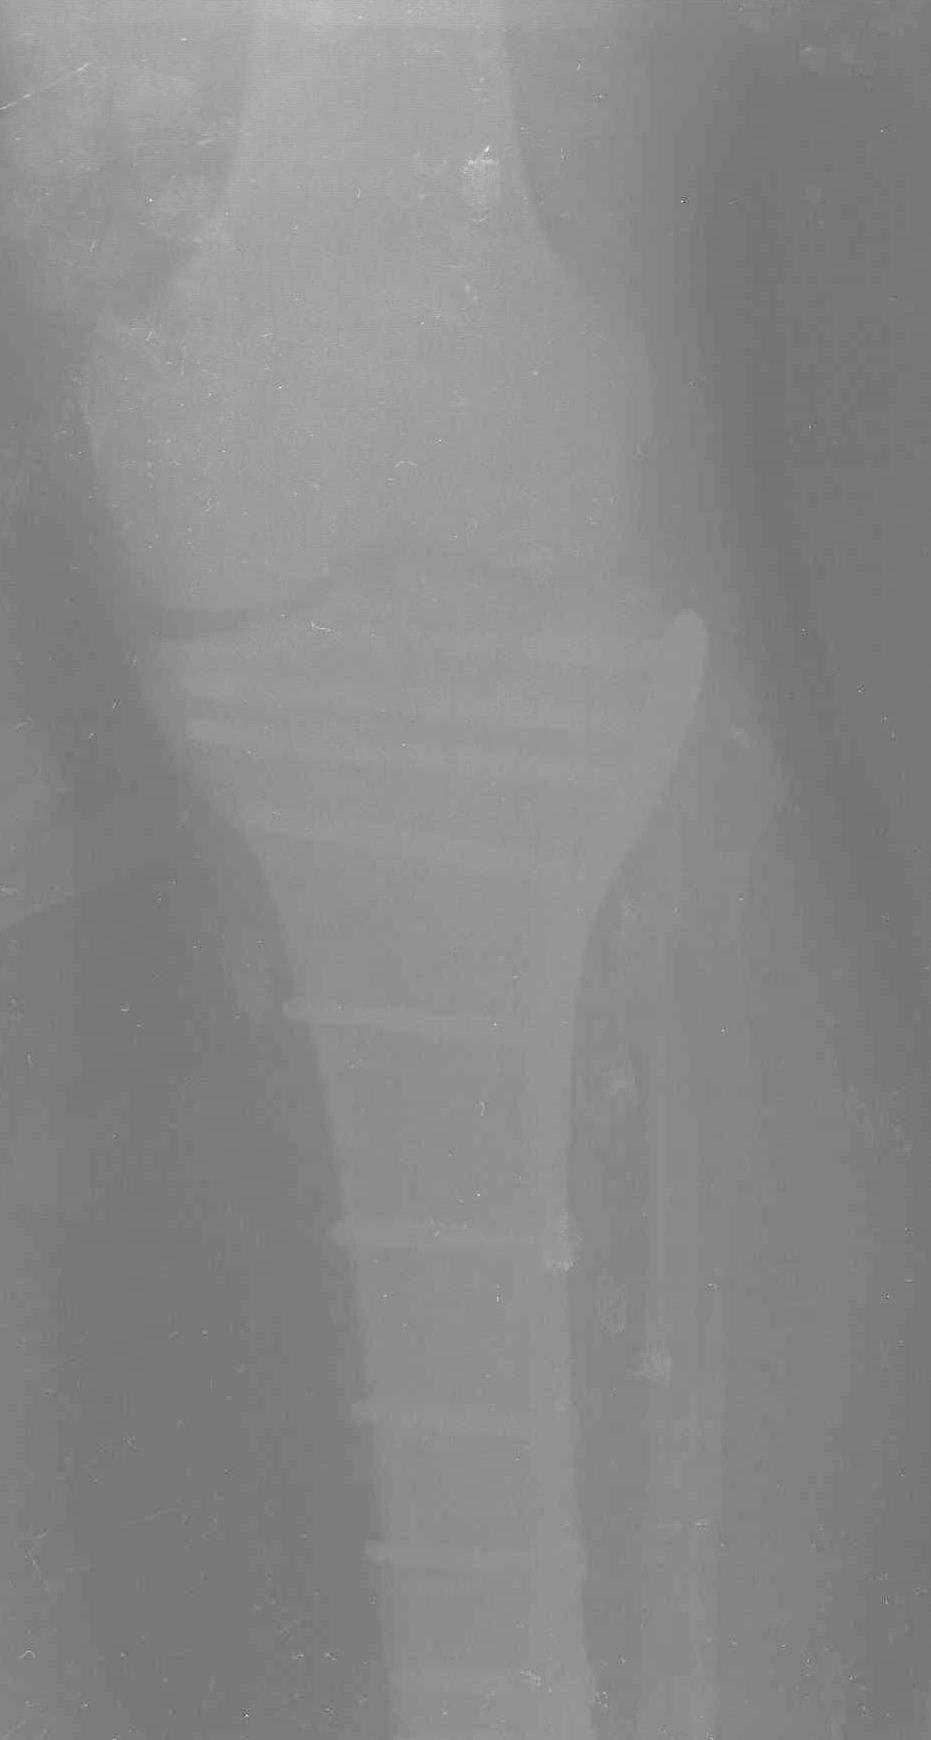

Уважаемые коллеги! В прошлую пятницу больной прооперирован - как и планировалось мыщелковая LCP от ChM. Малоинвазивно не получилось - один большой доступ :(. (но с минимальным скелетированием б/б кости). Наружный мыщелок собрали, но по контролю видно, что задне-медиальный отдел метаэпифиза смещен. Фиксировать не стали (?). 4-е сутки после операции - по м/тканям без проблем. Дополнительная иммобилизация синтетическим тутором.

Интересно услышать ваши мнения, анализ ошибок...

P. S. перелом диафиза на контроле не совсем захвачен, но проблем там нет. Приношу извинения за низкое качество Р-грамм - выполнены на сканере (фотоаппарат не работает :)) .

Трудно поверить, что разрекламированная Ортопедическая школа Восточной Украины позволяет такие странные снимки? На прямом снимке сохранен общий контур плато, но не известна судьба импрессии суставной поверхности. На полубоковой?, оставлен без репозиции задне-медиальный отдел, и навряд ли после такой фиксации можно удовлетвориться результатом.

Такая ситуация характерна для многих, когда принимается ошибочное решение, т.е пытаются фиксировать одним имплантом переломы двух мыщелков. Латеральная пластина приемлема только для тех случаев, когда сохраняется интактным медиальный диафизарный кортекс и отсутствует фрагментация на верхушке медиального перелома.

Представленные снимки не информативны, нужны отдельные качественные снимки коленного сустава и голени без ротации.

Доступ к медиальной стороне задний или медиальный, через pes или в пространстве между medial gastroc мышцы.